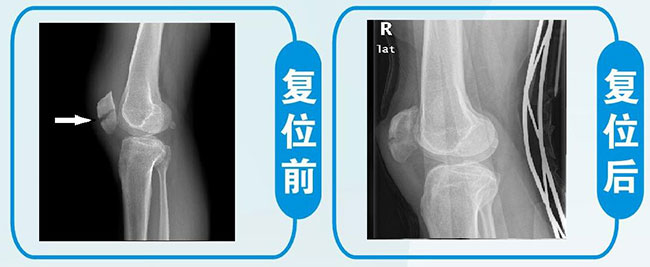

广东省人民医院正骨科成立于1958年,长期以来运用正骨复位固定技术治愈了无数的骨折、脱位患者,获得了广大患者的好评和同行的认可。正骨技术具有创伤少,费用低,功能恢复快的特点,尤其适用于老年骨折等不适宜手术的患者。 我科对这类骨折有独特的复位和固定方法,复位理想,关节功能恢复好。

4、 老年髌骨骨折